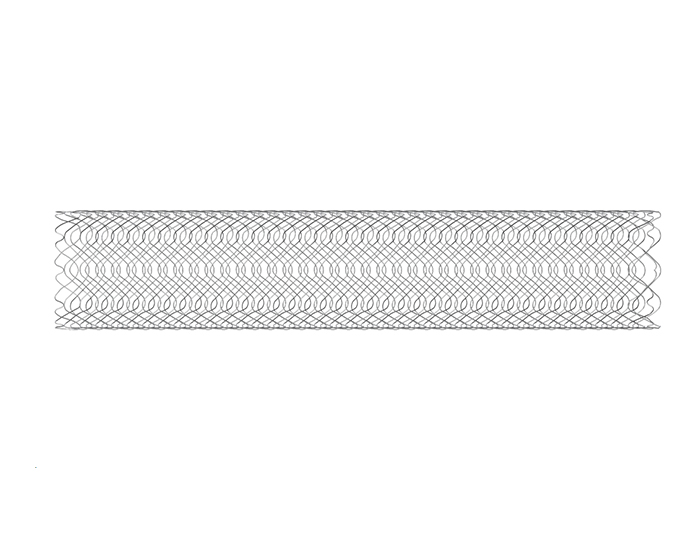

Zegatec specializes in producing medical needle and

ZEGATEC Products

With a number of products and patents,

we are constantly developing and growing new products.